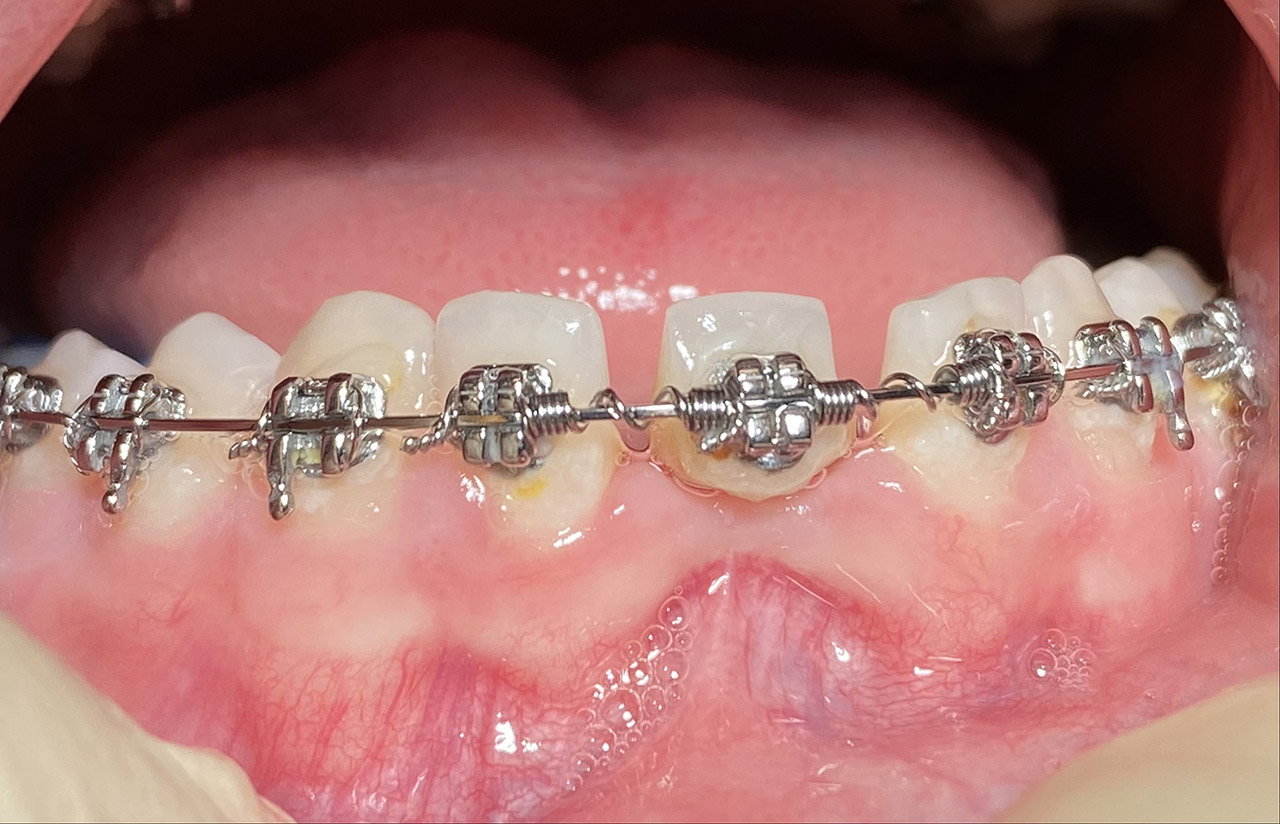

Prophylaxe/professionelle Zahnreinigung:

Zur Motivation, Information und Instruktion einfärben der Beläge (bakterieller Biofilm) bei jungem Patienten in kieferorthopädischer Behandlung.

Reinigung der Zähne mit Pulverstrahltechnik minimalinvasiv und zahnschonend und wo noch nötig gezielt mit Ultraschall.

Das Resultat 45 Minuten später.